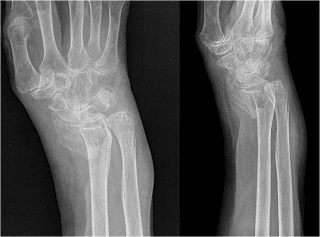

Para resolver la fractura lo primero es determinar la “personalidad” y características de la fractura y del paciente; con la historia del trauma, forma en que ocurrió el accidente con sus detalles, los antecedentes personales y familiares especialmente de fracturas previas personales o familiares, hábitos y aspectos nutricionales, alérgicos y medicamentosos. El examen clínico y de imágenes que en algunas fracturas especialmente articulares requieren de exámenes especiales como la TAC.(18)

Los objetivos del tratamiento son lograr y mantener una reducción que tenga una inclinación radial mayor a 5ª, radio sin pérdida de altura o máximo 2 mm, angulación palmar mínimo en neutro.